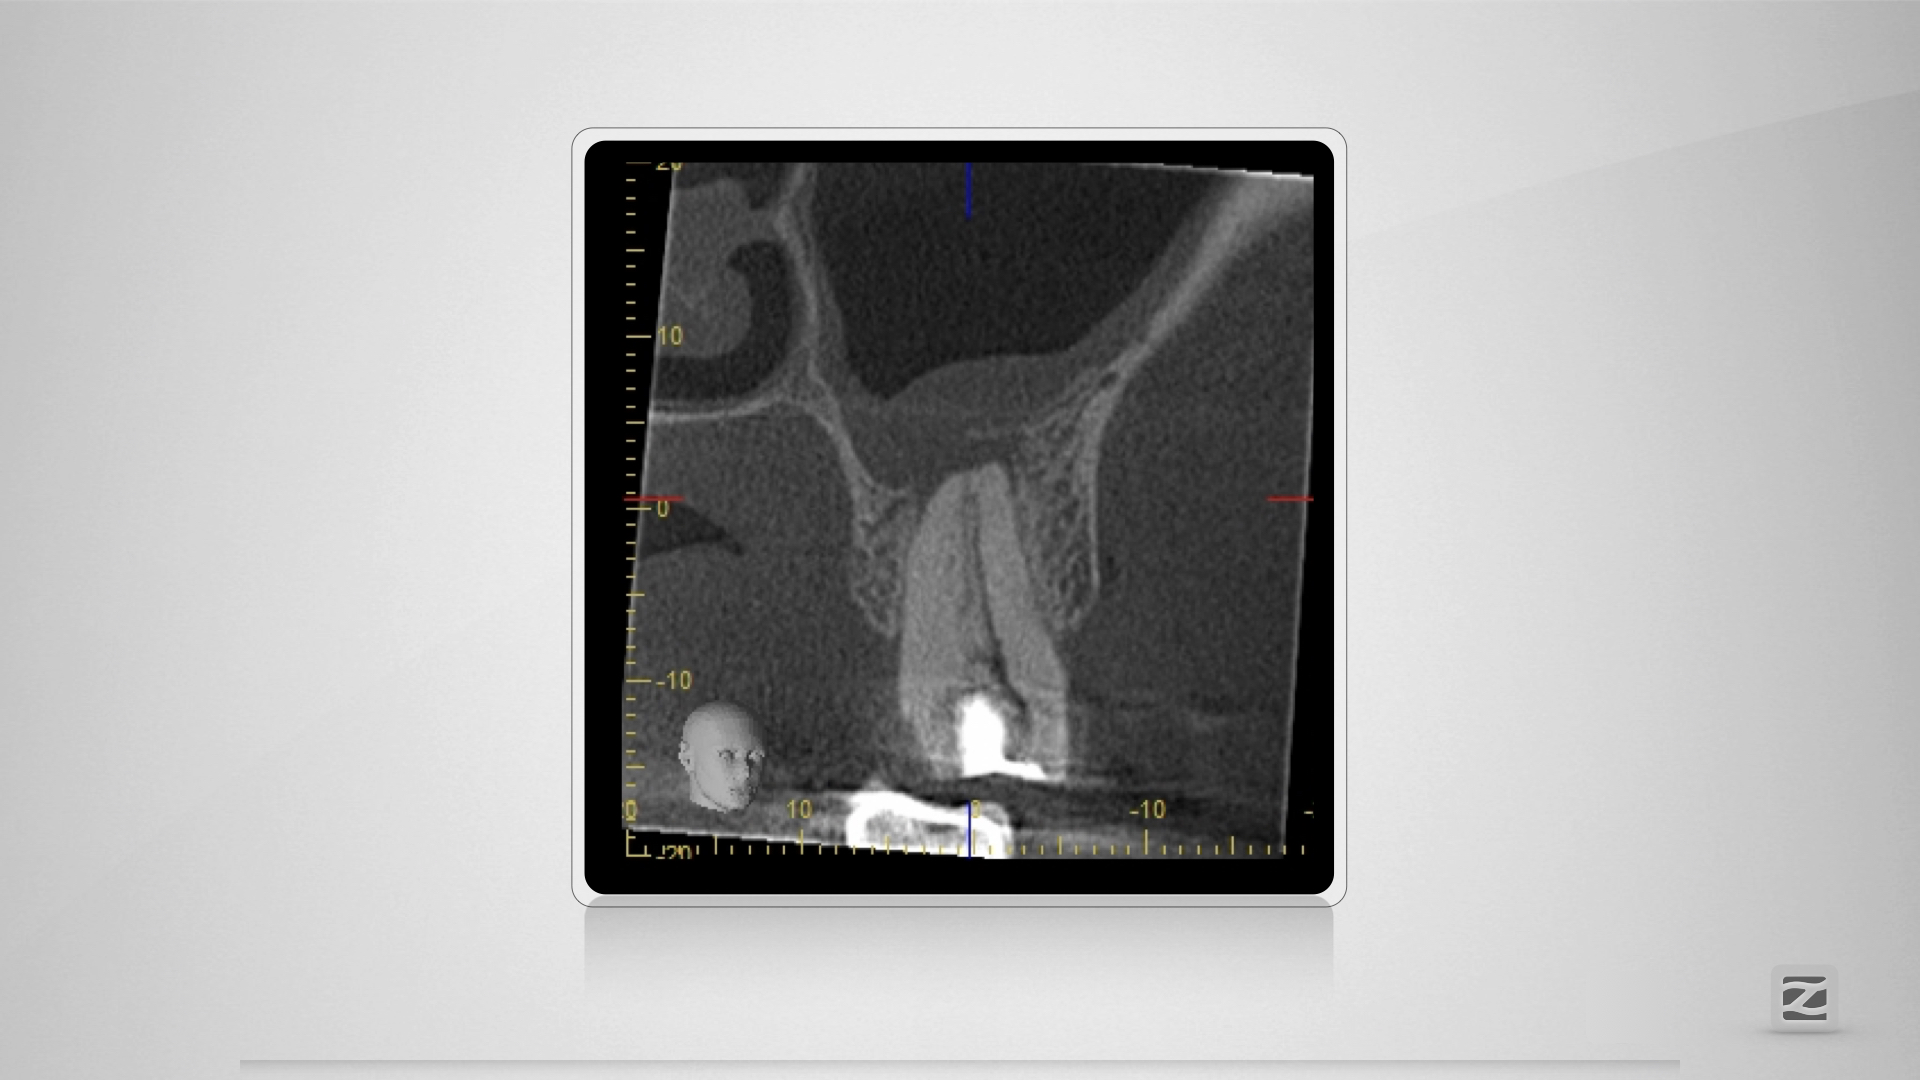

Großer Dentikel, tiefer Split.